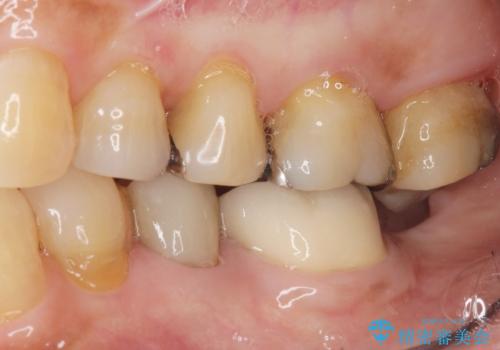

インプラントは嫌 親知らずの移植 50代女性

![[親知らずの移植] インプラントを用いない咬合回復の症例 治療前](https://seimitsushinbi.jp/wp/wp-content/uploads/2017/09/dcee39cf917a7a352bc6fcb0183543af-500x350.jpg)